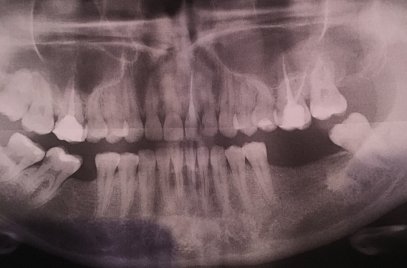

Здравствуйте! Есть ли у меня киста? Если да, то как срочно нужно делать операцию и как она называется?

Какой зуб вы имеете ввиду? Уточните. 18 и 48 зуб необходимо удалить. Далее расскажу после уточнения.